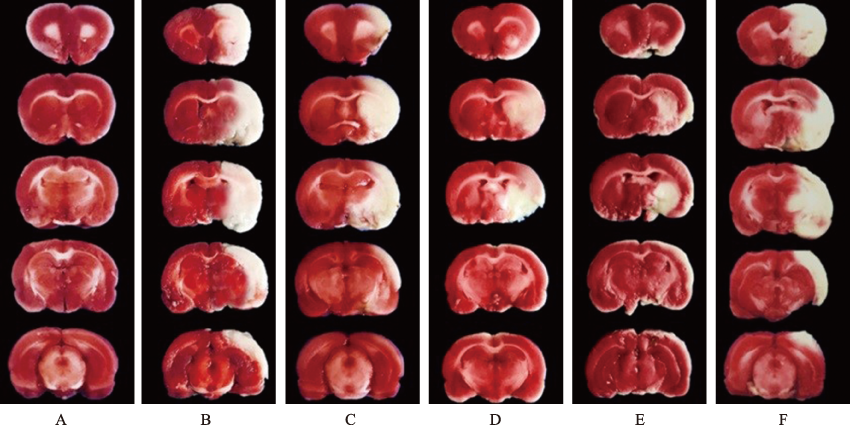

| 图1 6组大鼠脑梗死体积(TTC染色) A:假手术组;B:模型对照组;C:小剂量双路通脑方组;D:中剂量双路通脑方组;E:大剂量双路通脑方组;F:大剂量双路通脑方+AICAR组。 |

| Fig.1 Cerebral infarct volume in six groups of rats (TTC staining) A:sham operation group;B:model control group;C:low-dose Shuanglu Tongnao decoction group;D:medium-dose Shuanglu Tongnao decoction group;E:high-dose Shuanglu Tongnao decoction group;F:high-dose Shuanglu Tongnao decoction+AICAR group. |